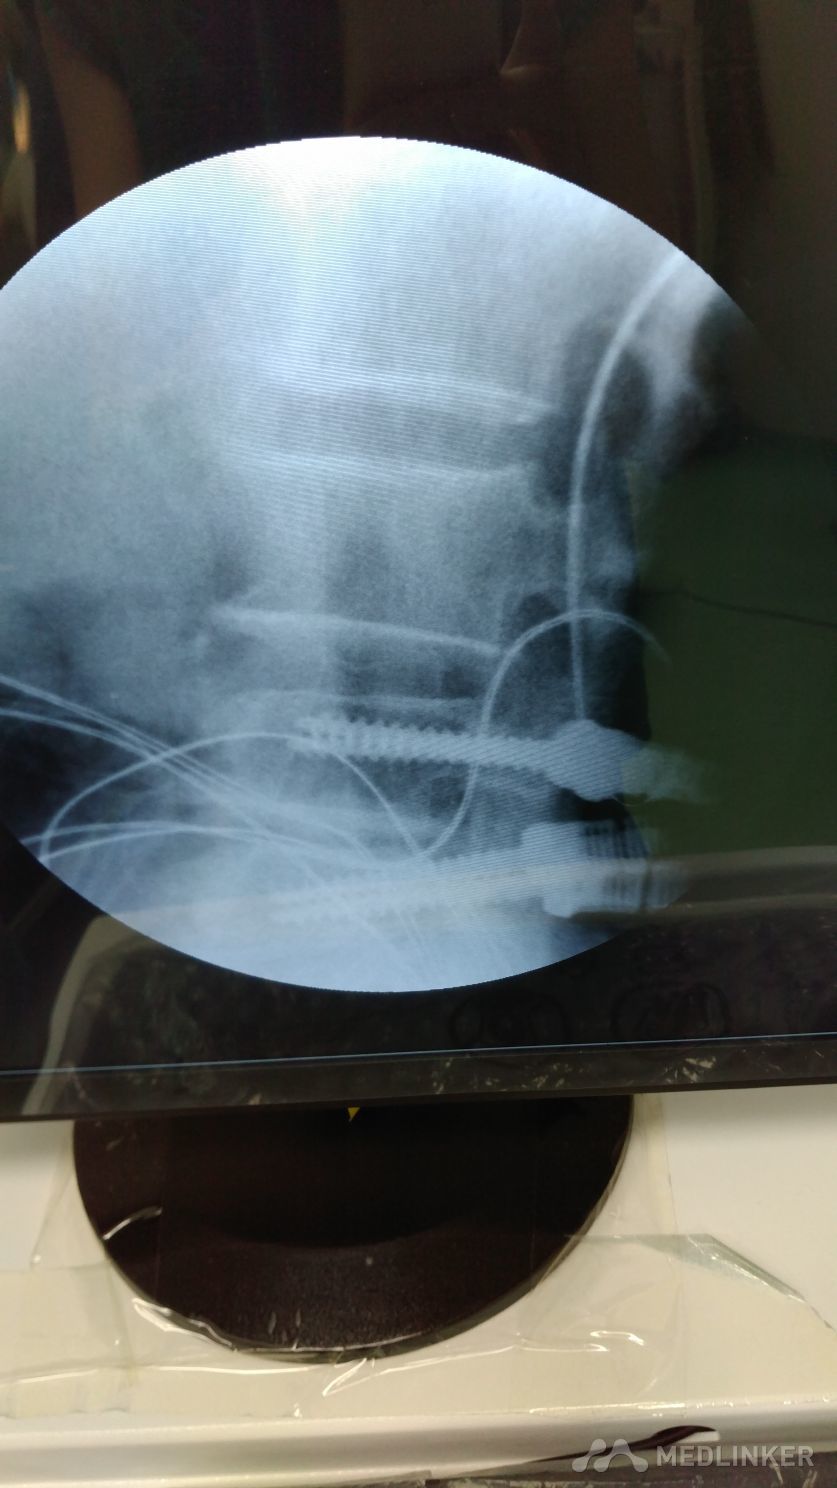

腰椎术后

腰椎间盘突出